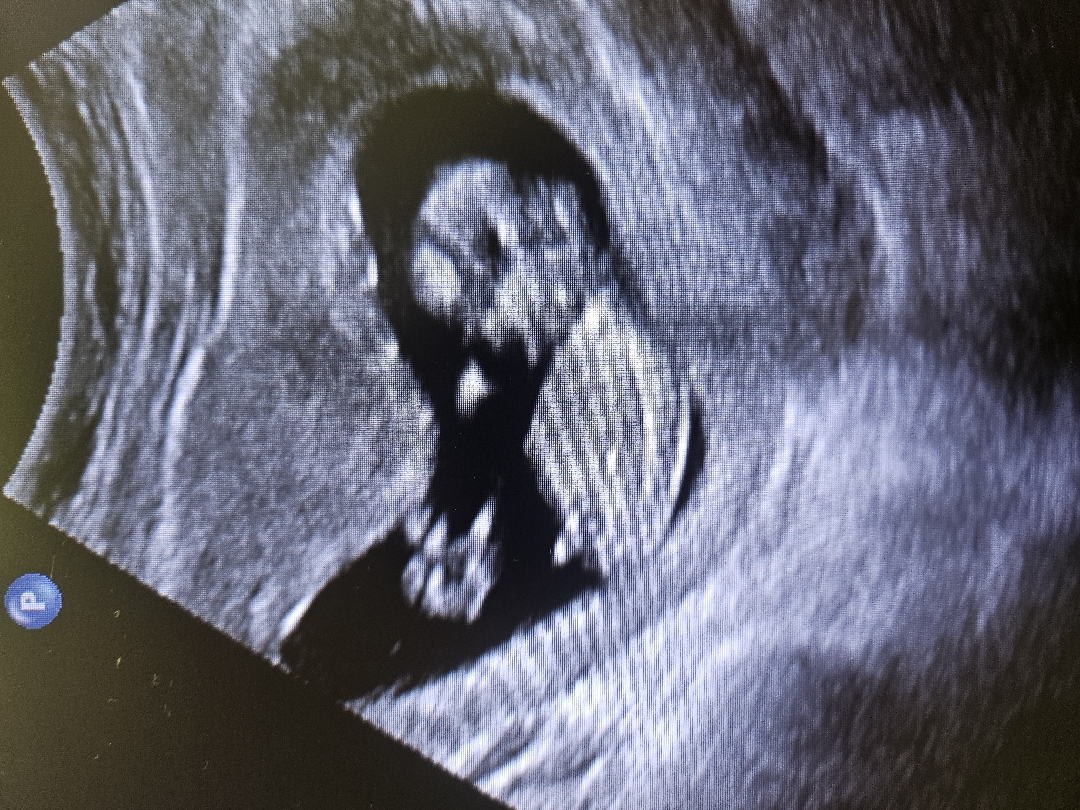

12주 3일! 저도 각도좀 ㅎㅎ

저도 봐주세용 ㅎ 아들이려나...